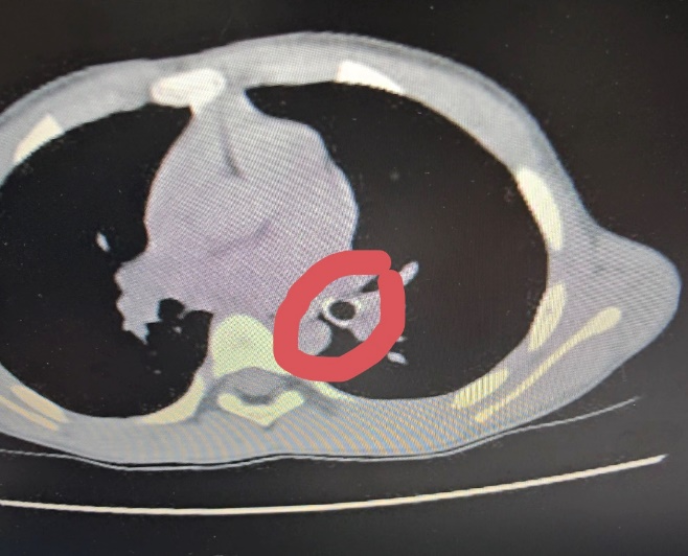

Qua thăm khám lâm sàng, các bác sĩ nghi ngờ trẻ hóc dị vật đường hô hấp, khả năng là đầu ngòi bút. Bệnh nhi được chỉ định chụp CT ngực, kết quả ghi nhận dị vật hình ống, bề dày thành khoảng 1,8mm, chiều dài khoảng 18mm, nằm tại phế quản thùy dưới trái, gây cản trở thông khí.

Hình ảnh dị vật trên phim X-quang. Ảnh: BVCC.